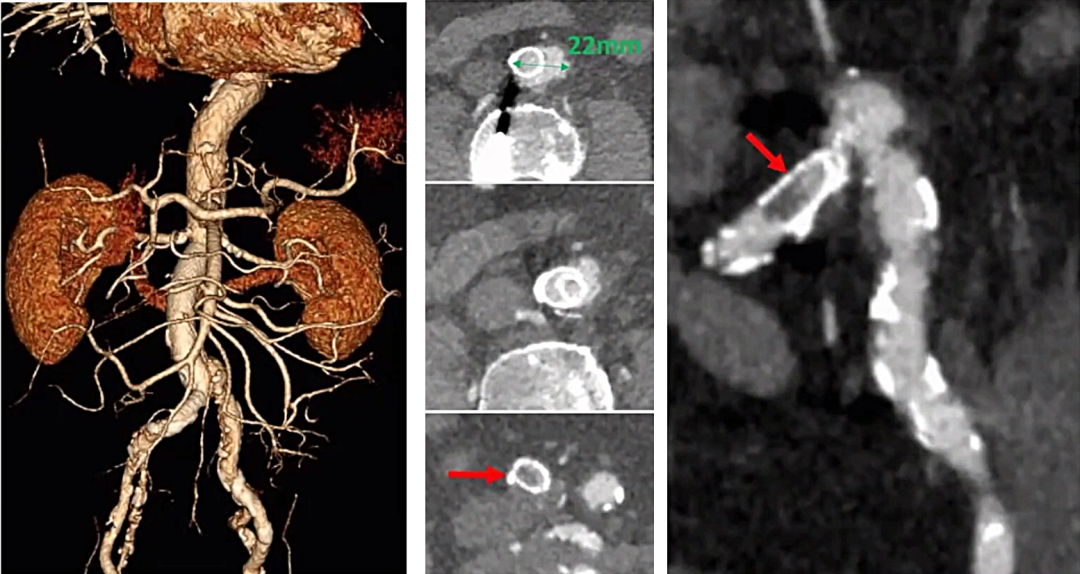

CTA:2022年1月患者因“右下肢间歇性跛行”复查CTA

右髂总动脉支架内再狭窄近闭塞,支架近端伸入到腹主动脉中。腹主动脉下端扩张,直径22mm

● 腹主动脉直径约12-13mm(裸支架Wallstent内径),腹主动脉末段直径约22mm,左侧髂总动脉直径8mm

● 原髂动脉裸支架Express LD直径为6-8mm,头端紧贴腹主动脉左侧壁,走行与腹主动脉几乎成90°